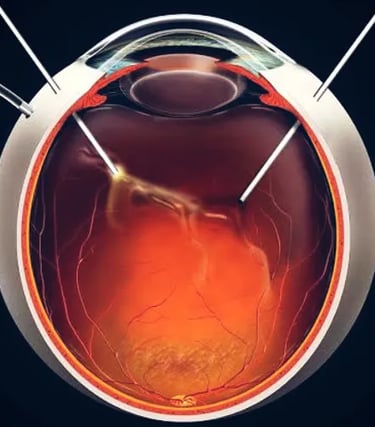

Fellowship em Retina Clínica e Cirúrgica pela UNICAMP